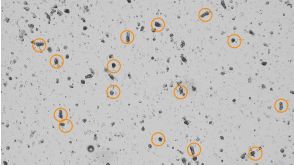

技术公告Forskolin-Induced Swelling of Human Intestinal Organoids Grown in IntestiCult™

技术公告Forskolin-Induced Swelling of Human Intestinal Organoids Grown in IntestiCult™产品类型:

Cell Culture Media and Supplements

细胞类型:

上皮细胞,肠道细胞